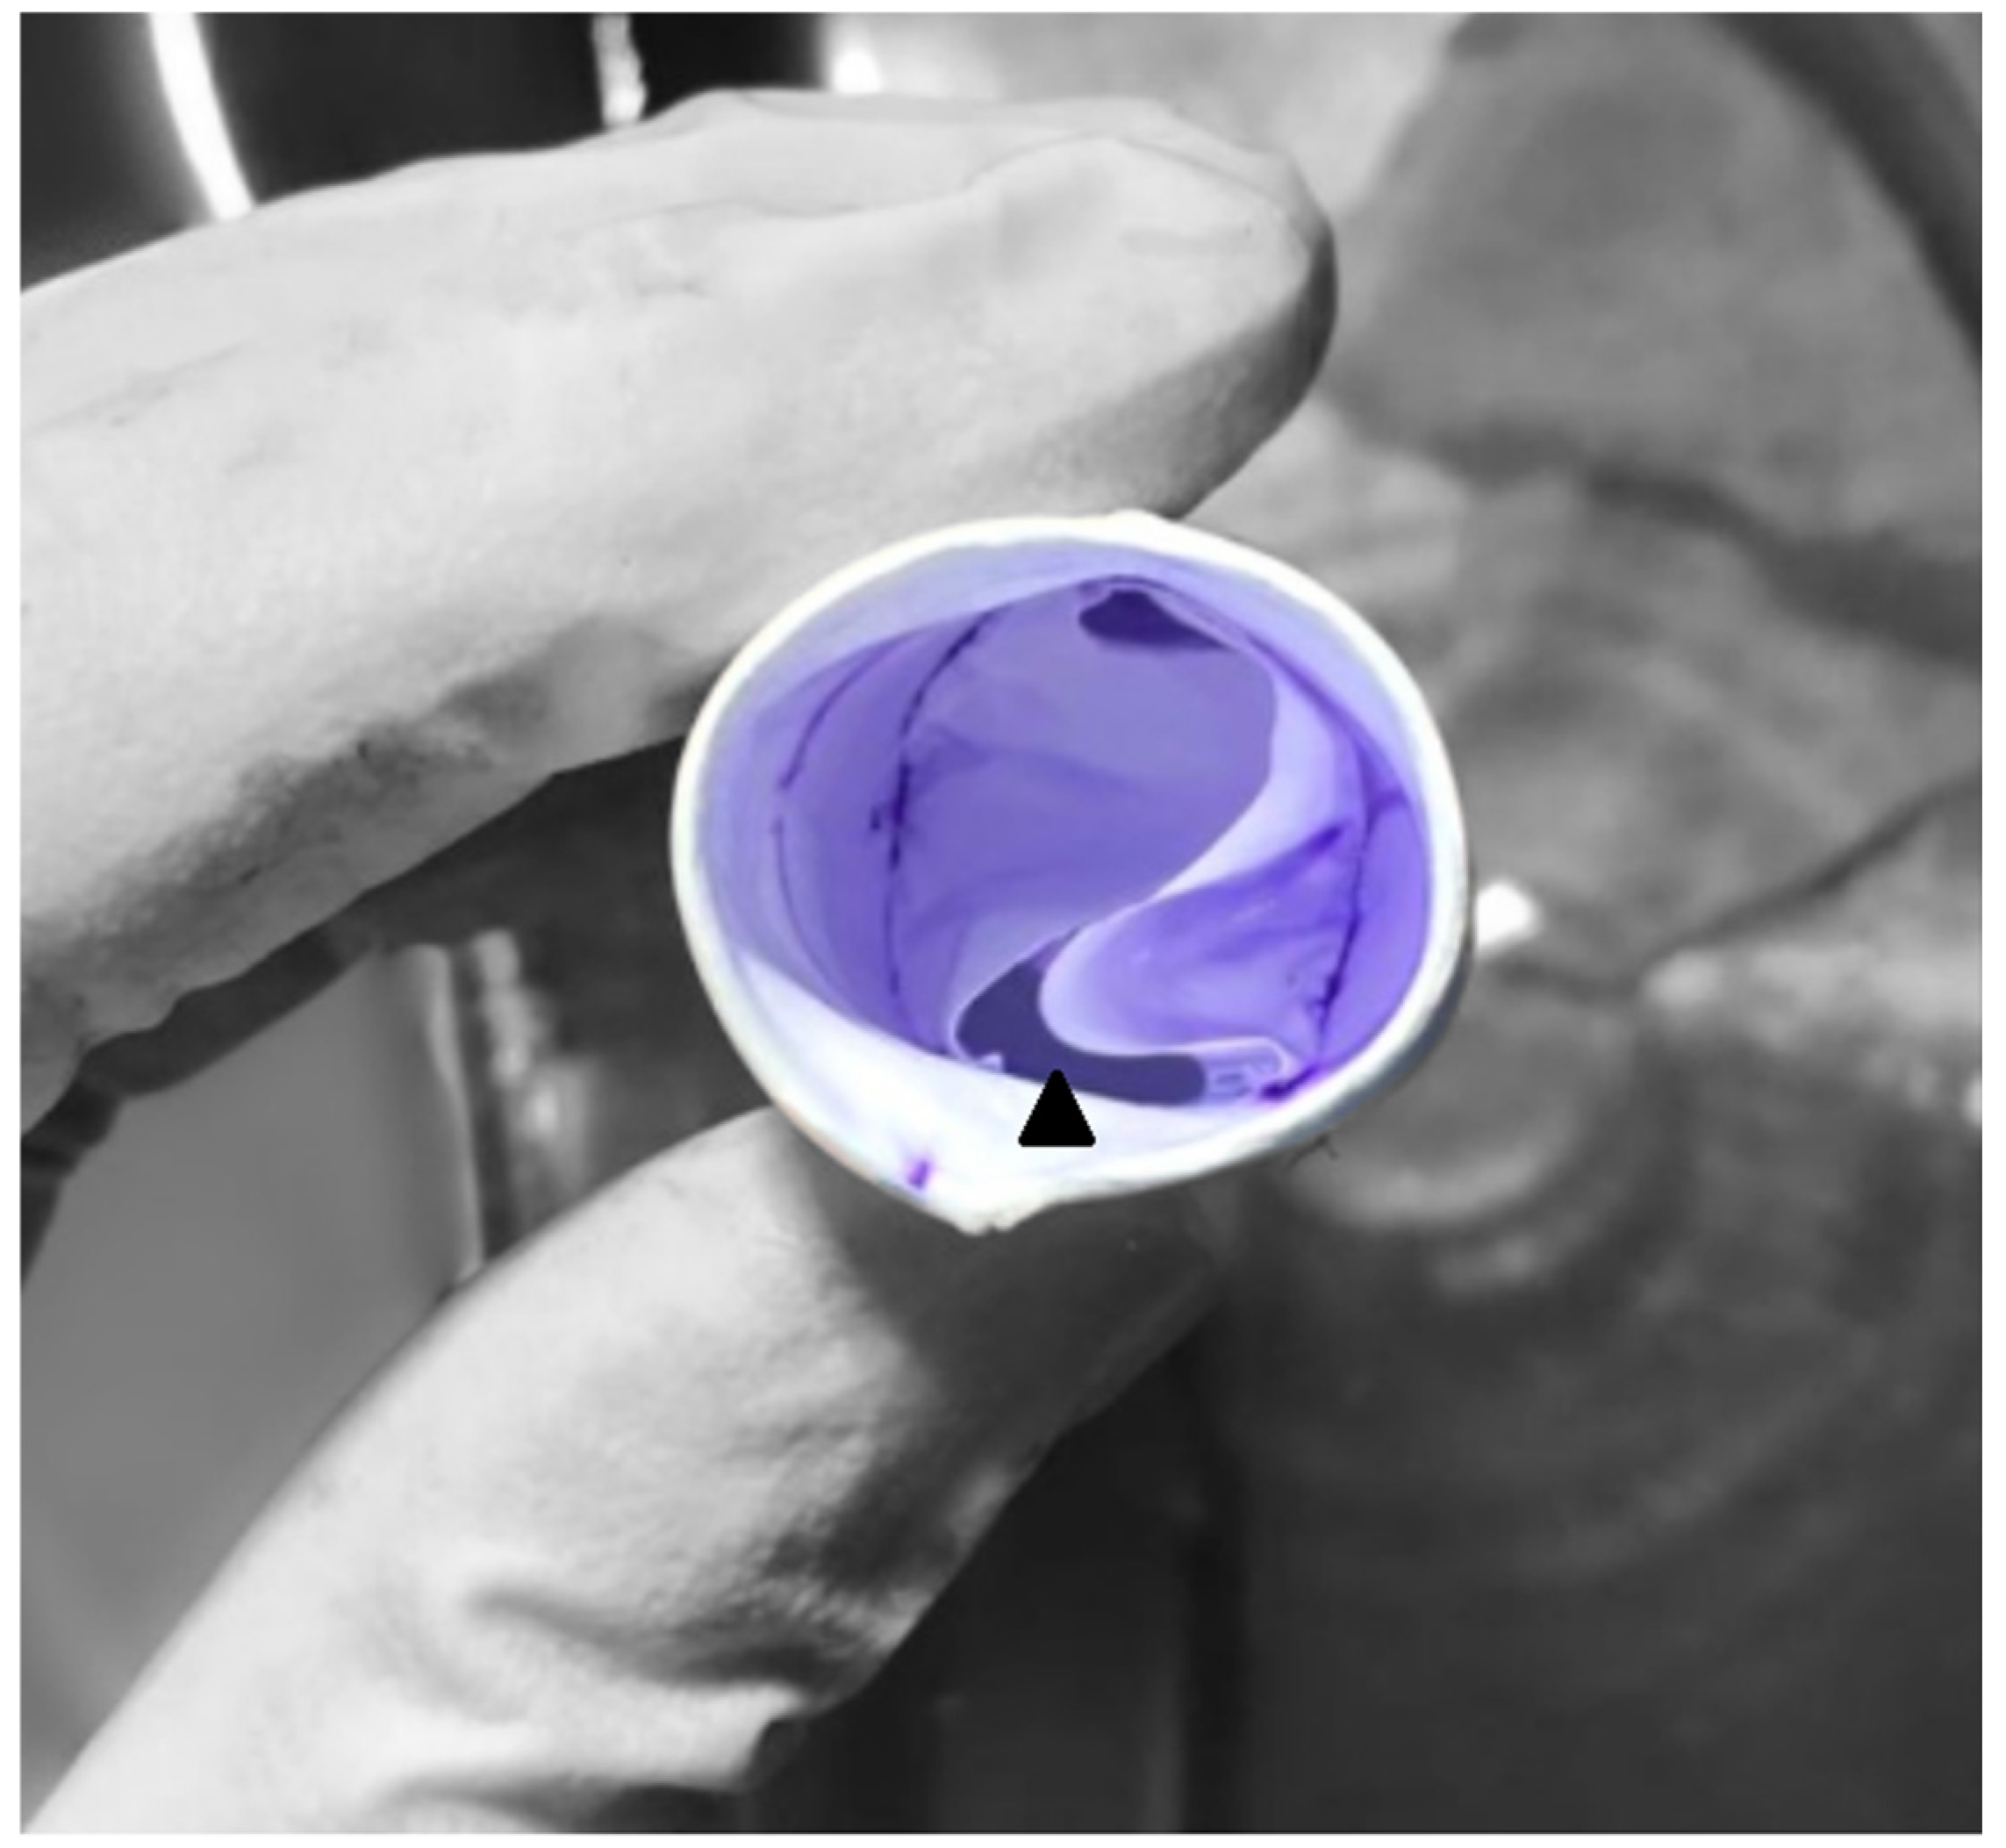

2.1. Surgical Technique